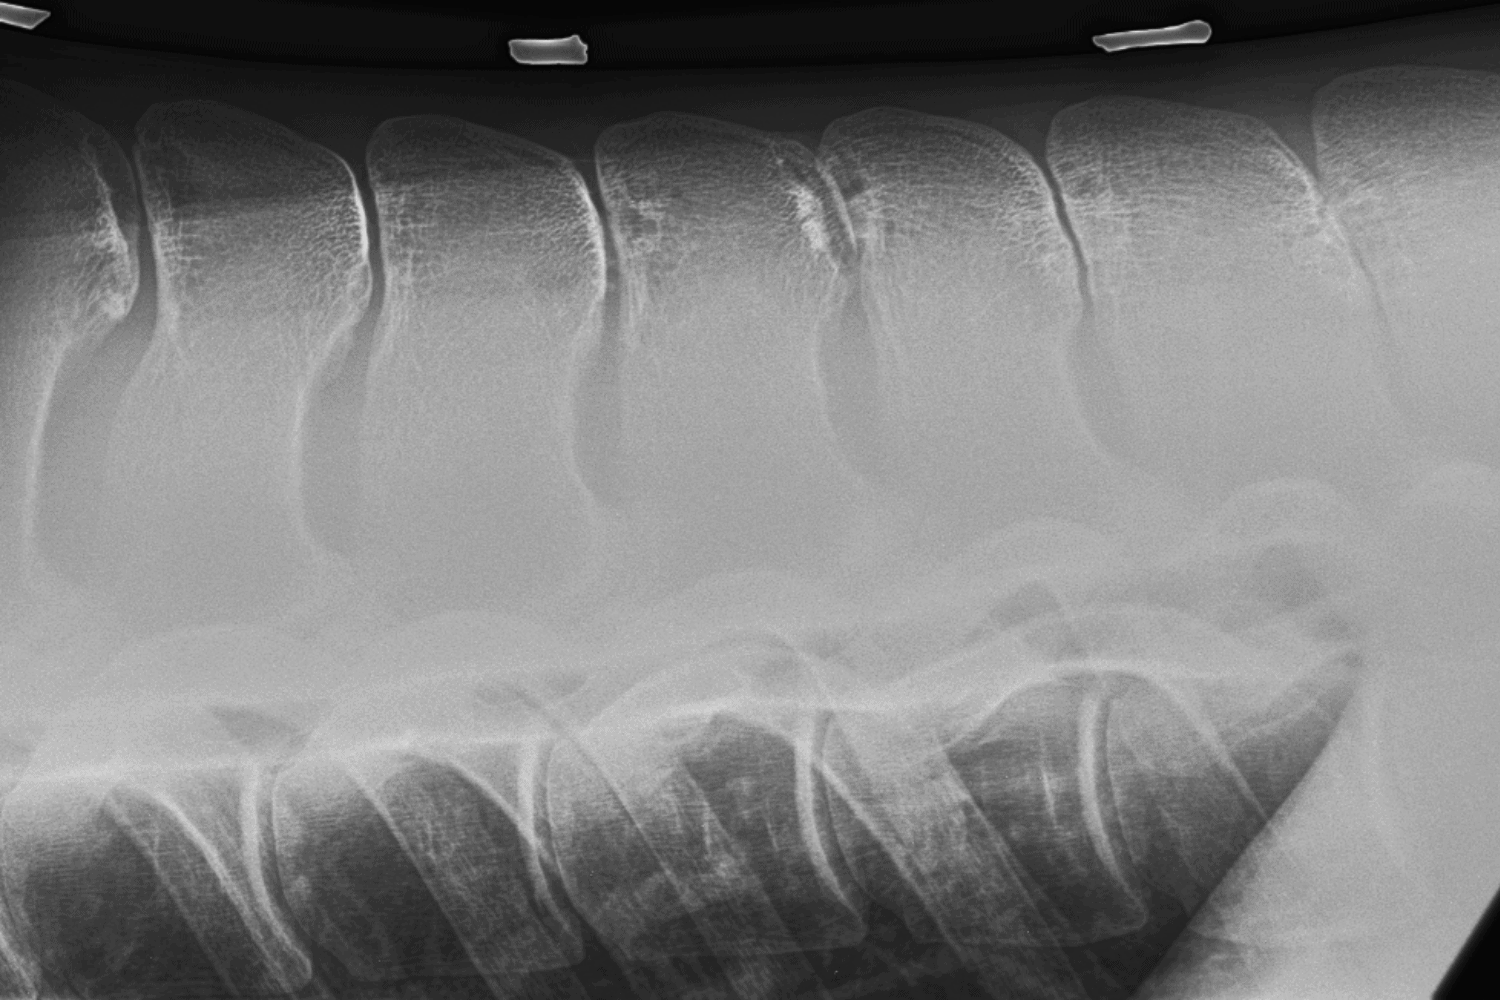

How To Check A Horse For Kissing Spine . learn about kissing spines, a condition that affects the bony projections of the vertebrae and causes back pain and poor performance in horses. kissing spines, or overriding spinous processes, are a common cause of back pain in horses. despite its reputation for causing severe and lasting back pain in horses, kissing spine doesn't have to be cause for retiring your horse from work. the most common clinical signs of kissing spine in horses include a reluctance to engage the hind limbs, difficulty rounding the back, resistance to. Andy kaneps as he explains the signs & symptoms, causes, diagnostics, treatment,. kissing spines is a condition of the horse's back where the spinous processes impinge on each other, causing pain. Learn how to diagnose, treat and prevent this condition from uc davis experts. kissing spines are when bony projections at the top of vertebrae touch or overlap, causing back pain or lameness in some horses. learn about kissing spine in horses from veterinarian dr. Learn how veterinarians use x rays, clinical signs, and other modalities to diagnose and treat this. Find out how to recognise, prevent and manage kissing spines with tips and webinar.

Learn how veterinarians use x rays, clinical signs, and other modalities to diagnose and treat this. kissing spines is a condition of the horse's back where the spinous processes impinge on each other, causing pain. kissing spines, or overriding spinous processes, are a common cause of back pain in horses. Learn how to diagnose, treat and prevent this condition from uc davis experts. the most common clinical signs of kissing spine in horses include a reluctance to engage the hind limbs, difficulty rounding the back, resistance to. learn about kissing spines, a condition that affects the bony projections of the vertebrae and causes back pain and poor performance in horses. Find out how to recognise, prevent and manage kissing spines with tips and webinar. despite its reputation for causing severe and lasting back pain in horses, kissing spine doesn't have to be cause for retiring your horse from work. Andy kaneps as he explains the signs & symptoms, causes, diagnostics, treatment,. kissing spines are when bony projections at the top of vertebrae touch or overlap, causing back pain or lameness in some horses.

How To Check A Horse For Kissing Spine despite its reputation for causing severe and lasting back pain in horses, kissing spine doesn't have to be cause for retiring your horse from work. despite its reputation for causing severe and lasting back pain in horses, kissing spine doesn't have to be cause for retiring your horse from work. Find out how to recognise, prevent and manage kissing spines with tips and webinar. kissing spines is a condition of the horse's back where the spinous processes impinge on each other, causing pain. kissing spines, or overriding spinous processes, are a common cause of back pain in horses. the most common clinical signs of kissing spine in horses include a reluctance to engage the hind limbs, difficulty rounding the back, resistance to. learn about kissing spine in horses from veterinarian dr. kissing spines are when bony projections at the top of vertebrae touch or overlap, causing back pain or lameness in some horses. learn about kissing spines, a condition that affects the bony projections of the vertebrae and causes back pain and poor performance in horses. Andy kaneps as he explains the signs & symptoms, causes, diagnostics, treatment,. Learn how veterinarians use x rays, clinical signs, and other modalities to diagnose and treat this. Learn how to diagnose, treat and prevent this condition from uc davis experts.

Kissing Spines in Horses How To Check A Horse For Kissing Spine learn about kissing spine in horses from veterinarian dr. Learn how veterinarians use x rays, clinical signs, and other modalities to diagnose and treat this. kissing spines, or overriding spinous processes, are a common cause of back pain in horses. kissing spines are when bony projections at the top of vertebrae touch or overlap, causing back pain. How To Check A Horse For Kissing Spine.